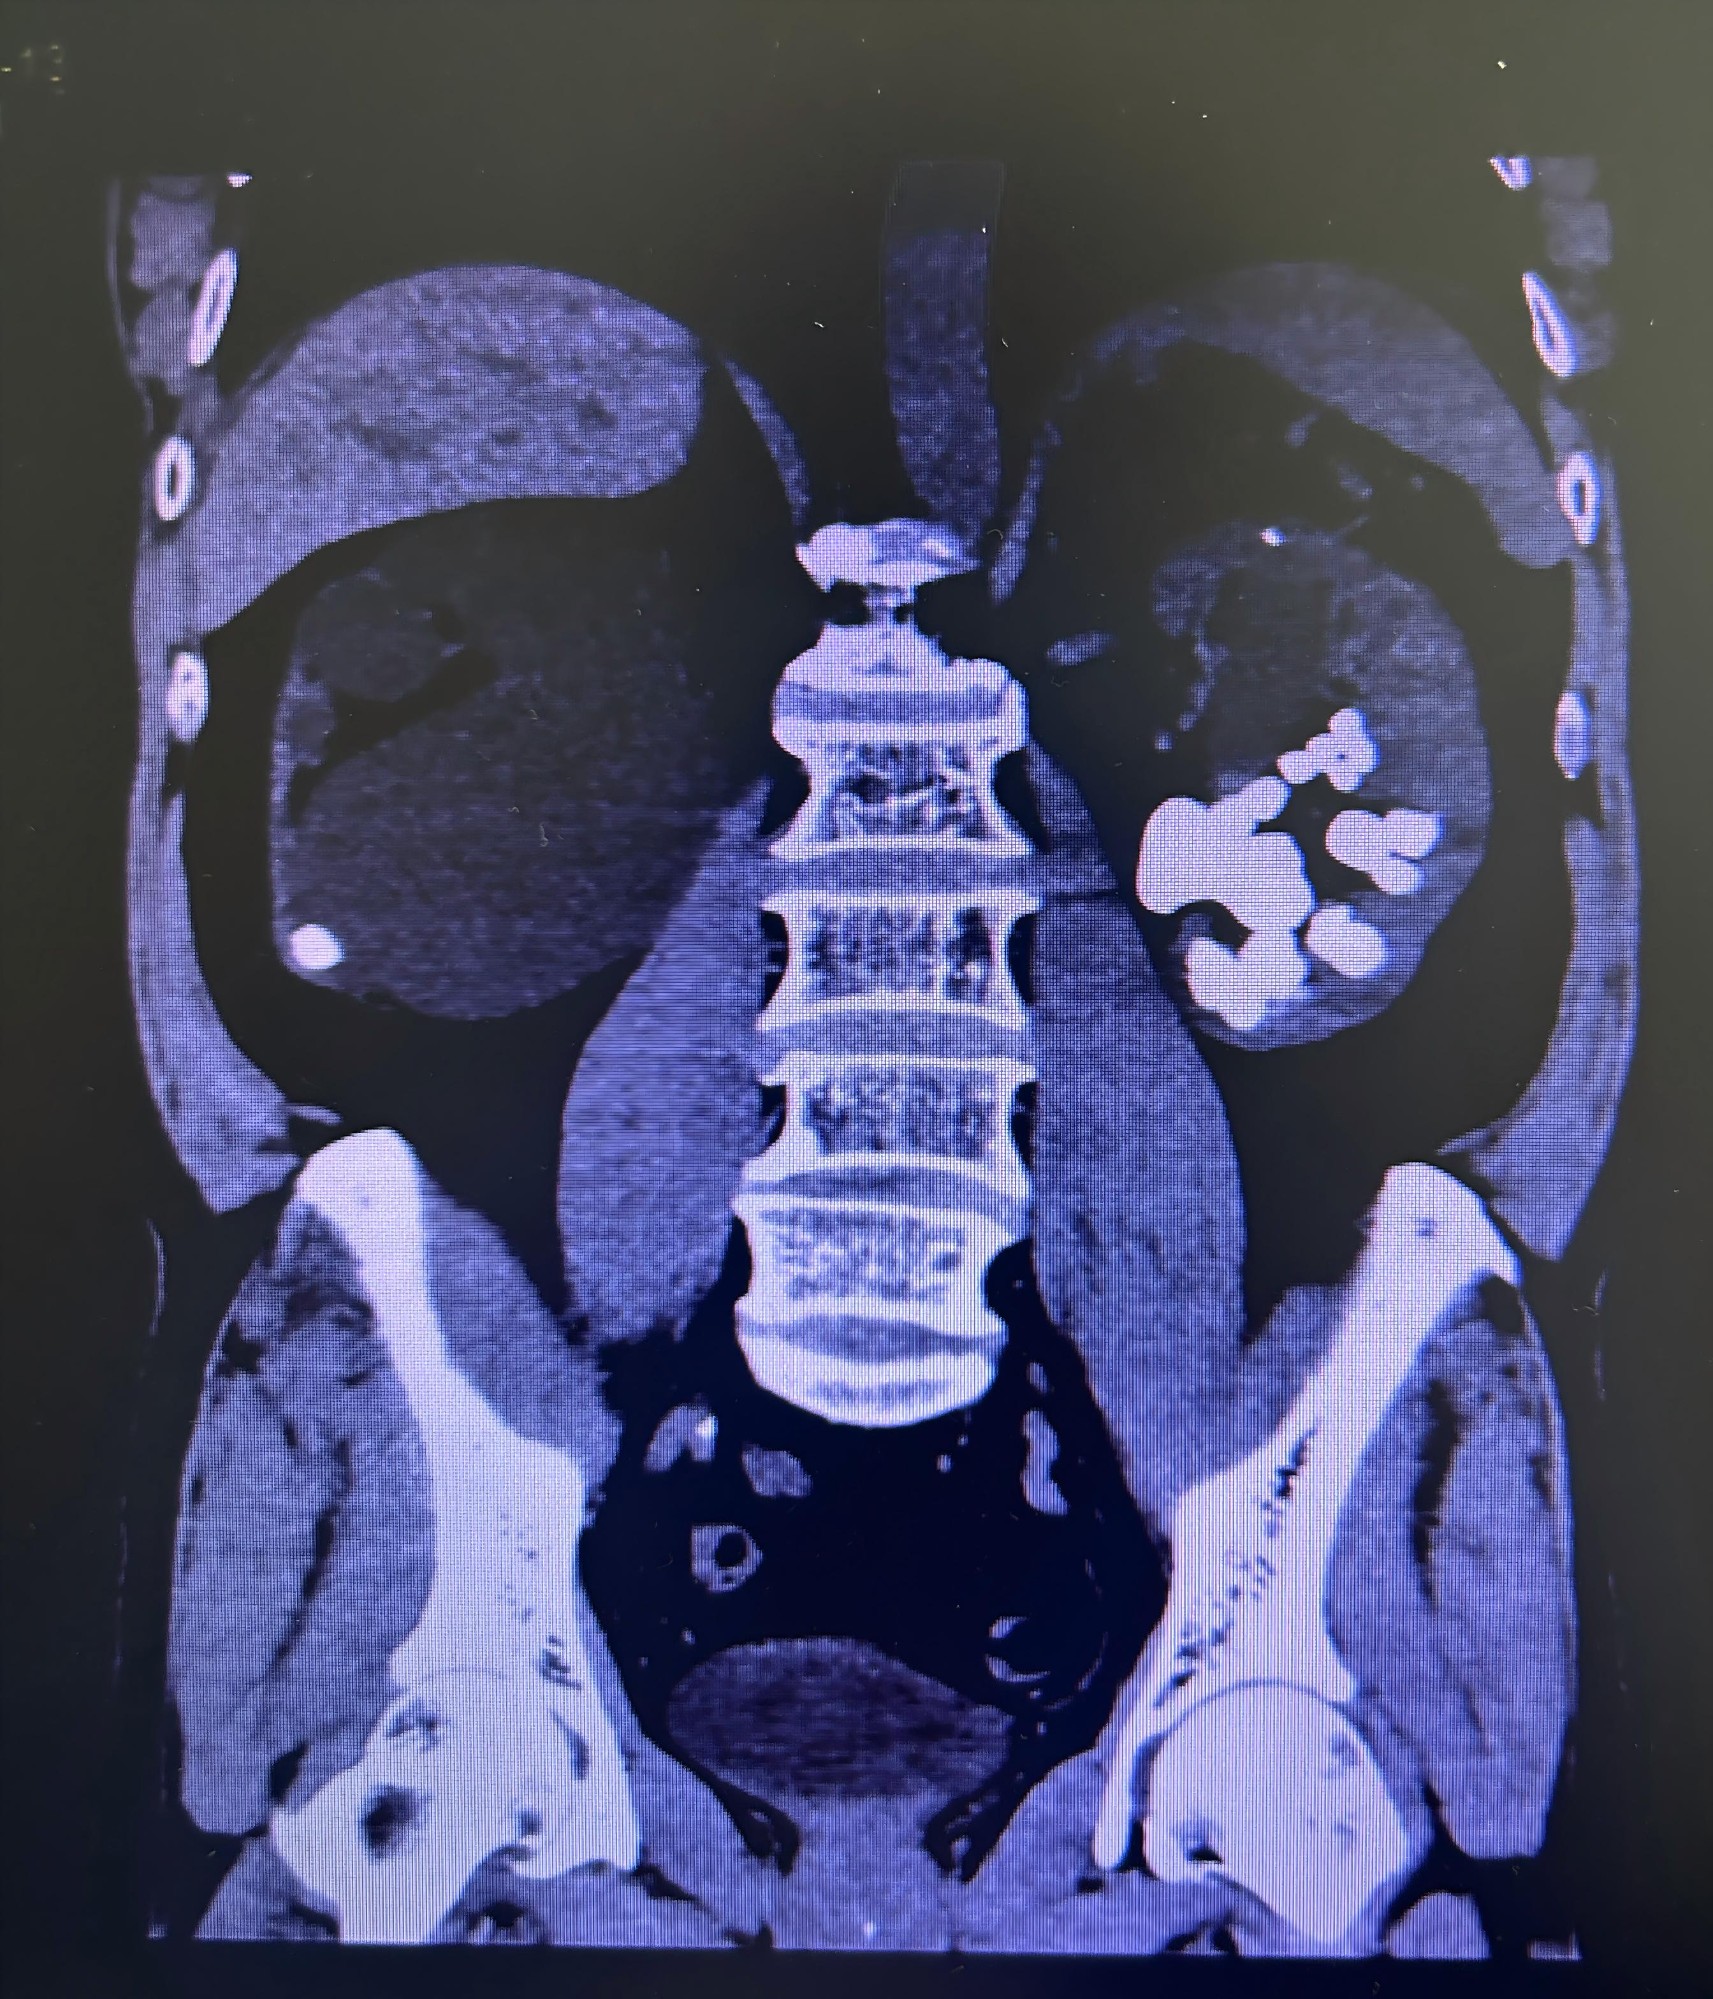

老覃(化名),69岁,功能性独肾——他的另一侧肾脏已基本丧失功能,多年来全凭这一颗肾脏维持生命。近日,他因“腰痛、无尿一天”紧急入院。检查结果让所有人心中一紧:左肾多发结石堵塞输尿管,梗阻已导致急性肾功能衰竭的苗头。如果不尽快解除梗阻,这颗唯一的肾脏将面临不可逆的损伤。

泌尿外科二科团队为老覃量身定制了一套“组合拳”式方案。手术采用斜仰卧截石位——患者无需在术中翻身,医生可同时从“上方”和“下方”两个路径操作,大幅节约时间。术中,医生们“软硬兼施”:软镜从下方进入,处理输尿管结石并深入各肾盏,清除藏在“犄角旮旯”的肾内结石;硬镜从上方进入肾内,处理大的结石并高效清除击碎的结石碎片。双镜联合、上下联动,医生在显示屏前如“排雷”一般,将结石一一击碎、取出。